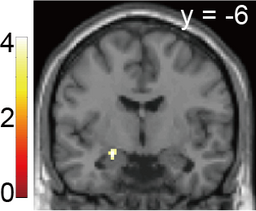

さらにfMRIデータの解析から、“曖昧であること”に対する評価は、脳の扁桃体の活動に依存することを見出しました(図3参照)。

図3 “曖昧であること”に対する評価を表現する扁桃体活動